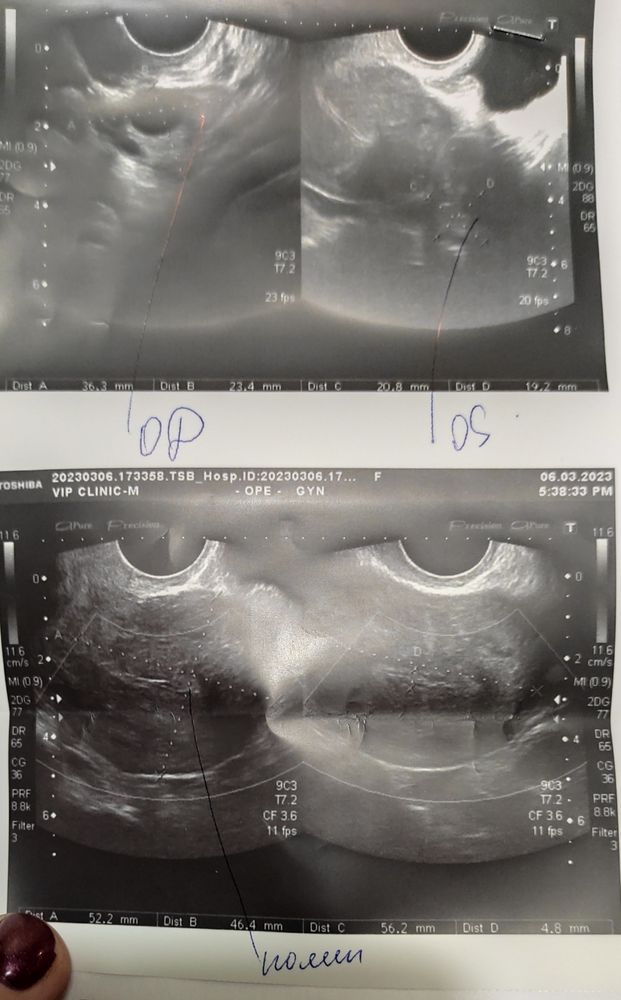

Эли, да, на 6 ДЦ, в начале марта Изображение

Анисия, странно только, что в продольном срезе его как будто видно, а в поперечном нет, или это качество фотографий такое не четкое просто. Я так понимаю про полип в этот раз она ничего вам не сказала. В общем, не думайте о плохом, все у вас там должно быть хорошо. Тест делали сегодня? Ярчает?